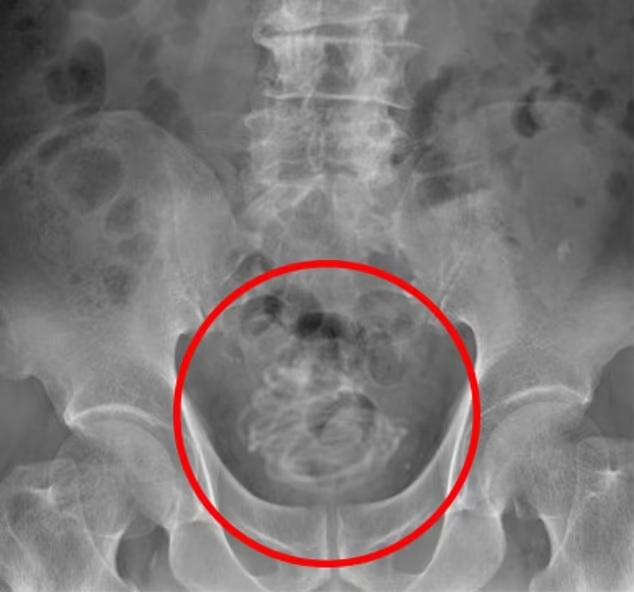

性上癮|日本老翁更嚇人90吋跳繩塞入陰莖

報道指,日本去年11月一個案更加嚇人,一名79歲老翁將90吋長的跳繩塞入陰莖,結果在膀胱內打圈塞住。由於要取出的難度極高,醫生甚至要靠電腦3D圖模擬如何在膀胱開刀取出跳繩。雖然老翁並沒有向醫生解釋為何塞繩入陰莖,但相信他是為了性快感。有英國醫生說,這是他聽過最極端的個案。